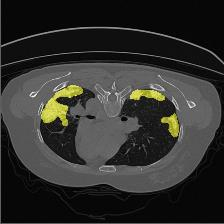

Medical image segmentation is one of the most fundamental tasks concerning medical information analysis. Various solutions have been proposed so far, including many deep learning-based techniques, such as U-Net, FC-DenseNet, etc. However, high-precision medical image segmentation remains a highly challenging task due to the existence of inherent magnification and distortion in medical images as well as the presence of lesions with similar density to normal tissues. In this paper, we propose TFCNs (Transformers for Fully Convolutional denseNets) to tackle the problem by introducing ResLinear-Transformer (RL-Transformer) and Convolutional Linear Attention Block (CLAB) to FC-DenseNet. TFCNs is not only able to utilize more latent information from the CT images for feature extraction, but also can capture and disseminate semantic features and filter non-semantic features more effectively through the CLAB module. Our experimental results show that TFCNs can achieve state-of-the-art performance with dice scores of 83.72\% on the Synapse dataset. In addition, we evaluate the robustness of TFCNs for lesion area effects on the COVID-19 public datasets. The Python code will be made publicly available on https://github.com/HUANGLIZI/TFCNs.

翻译:医学图像分解是医学信息分析的最根本任务之一,到目前为止已经提出了各种解决办法,包括许多深层次的学习技术,如U-Net、FC-DenseNet等。 然而,高精度医学图像分解由于医疗图像中存在固有的放大和扭曲,以及存在与正常组织密度相似的损伤,因此仍是一项极具挑战性的任务。在本文件中,我们建议TFCN(全面革命稠密网络的传输者)通过向FC-DenseNet引进ResLear-Transerferent(R-Transerfor)和Culvacial线性关注区(CLAB)来解决这一问题。TFCN不仅能够利用CT图像中更多的潜在信息来提取特征,而且还能够通过CLAB模块更有效地捕捉和传播语性特征和过滤非神经性特征。我们的实验结果表明,TFCN可以在Syapseion/SymblyDDS上以83CN-72 ⁇ 的分数实现状态。此外,我们在Synapse-DRIS数据设置上,我们还将评估CUTFTFI/LIS的可靠度。